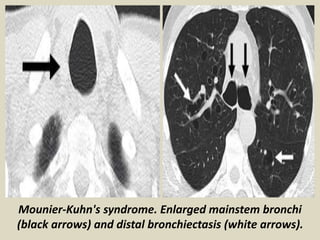

Mounier-Kuhn's syndrome. Enlarged mainstem bronchi

(black arrows) and distal bronchiectasis (white arrows).

Mounier-Kuhn syndrome, also known as tracheobronchomegaly, is a rare

congenital abnormality of the trachea and main bronchi characterized by

cystic dilatation of the tracheobronchial tree and recurrent respiratory infections.

Mounier-Kuhn Syndrome. Two axial CT images of the thorax demonstrate marked dilatation of the

trachea (T) and right (R) and left (L) main bronchi in this patient with Mounier-Kuhn syndrome. Notice

the bronchiectasis (red arrows and red circle) in which the bronchi are larger than their accompanying

blood vessel and there is tram=tracking of thickened bronchial walls seen in profile.